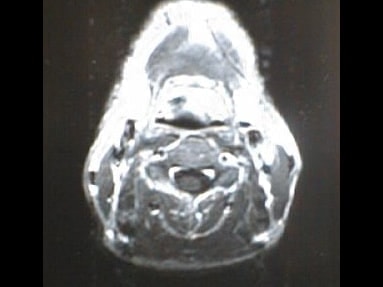

MRI画像比較

入院当時MRI画像②

入院3か月後癌消滅MRI画像②